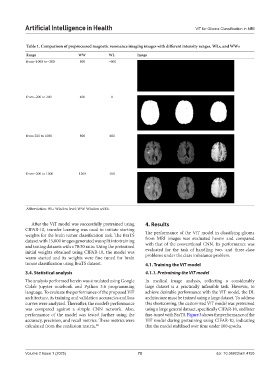

Table 1. Comparison of preprocessed magnetic resonance imaging images with different intensity ranges, WLs, and WWs

Range WW WL Image

from−1000 to−200 800 −600

from−200 to 200 400 0

from 200 to 1000 800 600

from−200 to 1000 1200 400

Abbreviation: WL: Window level; WW: Window width.